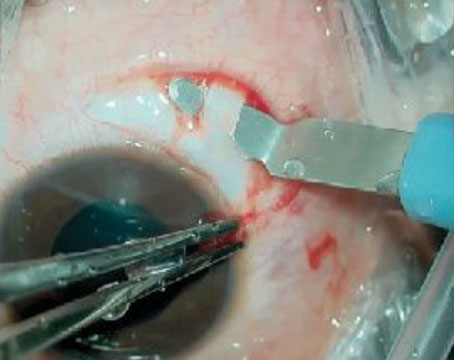

Pearls For Autologous Retinal Transplantation

An algorithm for successful graft sizing, harvesting and positioning in ART.

Retinal autograft with retinectomy and the SPOT technique for macular hole

The technique can be very useful in the setting of highly myopic PVR re-detachment.